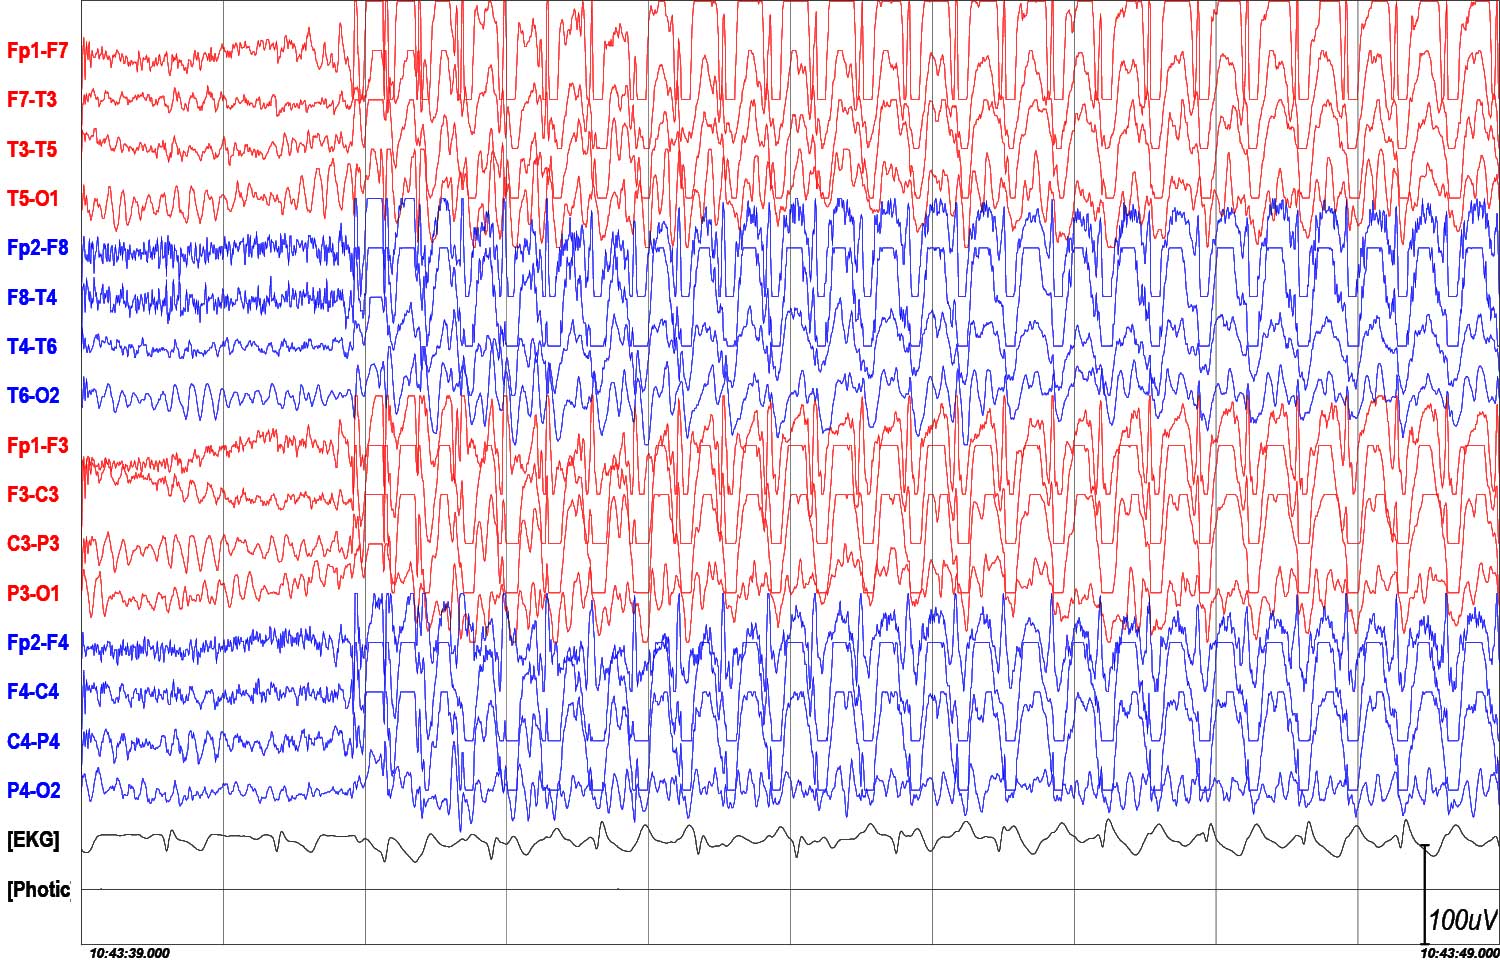

Napad nieświadomości

19-letnia kobieta z młodzieńczą padaczką nieświadomości. Na tle prawidłowej czynności podstawowej (rytm alfa 10 Hz) jednoczasowo rozpoczyna się uogólnione wyładowanie synchronicznych zespołów iglica-fala wolna i wieloiglica-fala wolna o częstotliwości 4 Hz na początku napadu, zmniejszającej się pod koniec wyładowania do 2,5 Hz i amplitudzie do 300 µV. Wyładowanie trwało 11 sekund.